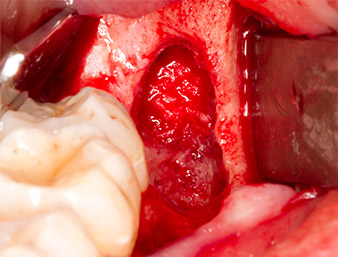

The tissue above the root remnant was not completely ossified and consisted for the most part of granulation tissue modified by inflammation (Fig. 4).

To obtain autogenous material for subsequent wound treatment, healthy bone chips were harvested from the surroundings of the root remnant with a piezo surgical instrument (Piezomed B5) (Fig. 5).